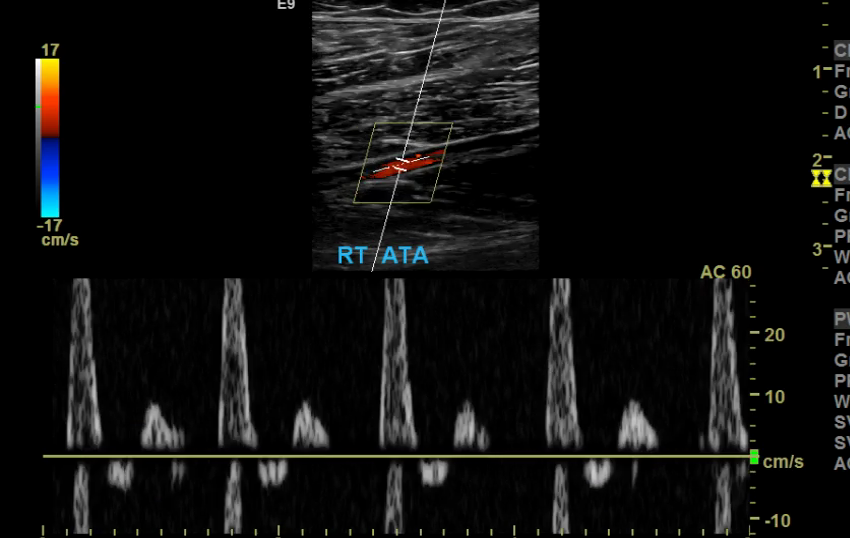

The iliac arteries bifurcate into external and internal iliac arteries (EIA and IIA). The EIA continues caudally turning into the common femoral artery (CFA) which further bifurcates into superficial femoral (SFA) and deep femoral artery (aka profunda femoris). The SFA then converts into the popliteal artery which bifurcates into the tibioperoneal trunk and anterior tibial artery (ATA). The tibioperoneal trunk bifurcates into posterior tibial artery (PTA) and the peroneal artery. The anterior tibial artery descends further to become the dorsalis pedis artery (DPA).

Anterior Tibial Artery